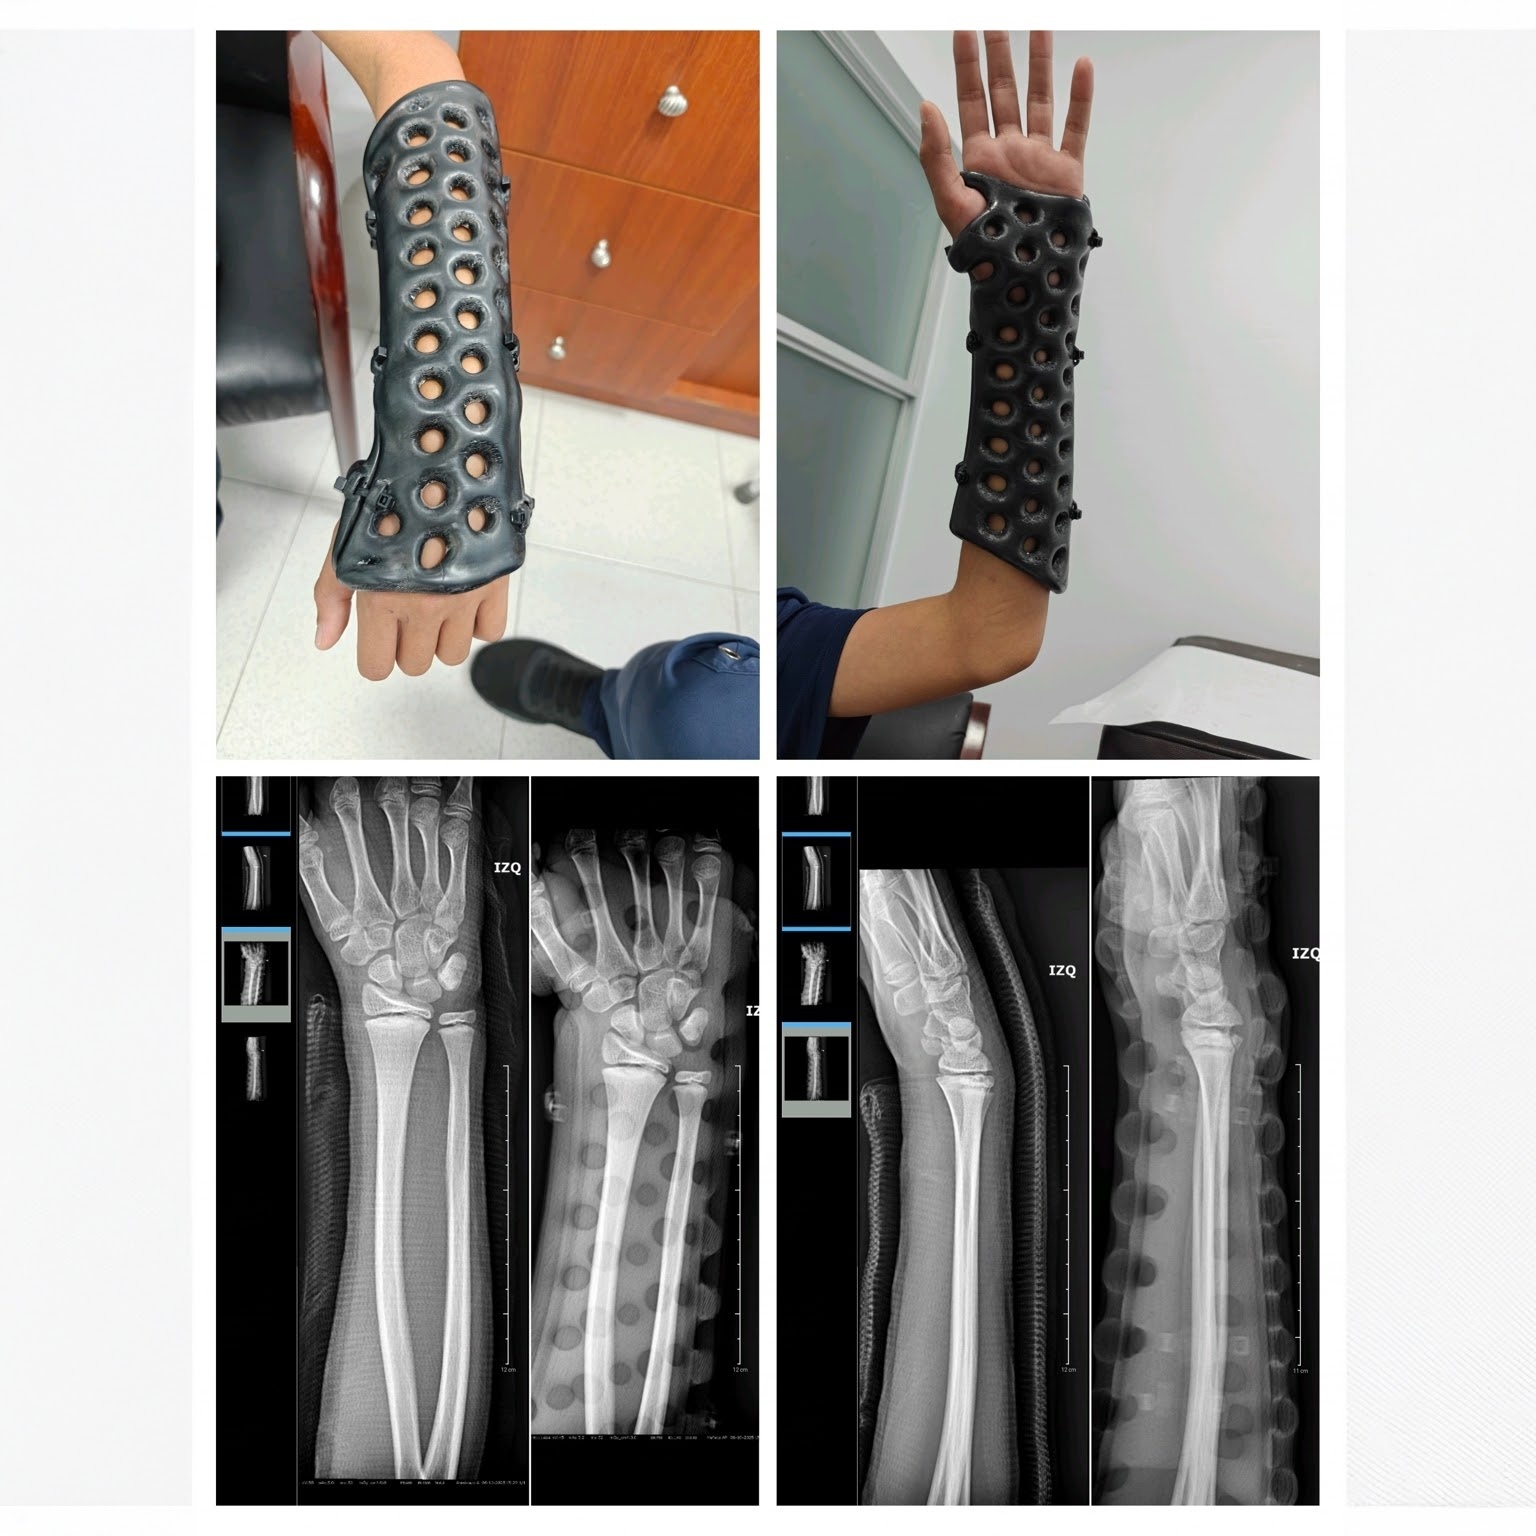

3D Printed Arm Cast

Lightweight and ventilated orthopedic support for broken arms

Experience the future of fracture care with our advanced 3D printed arm cast. Designed for superior comfort and durability, this cast offers exceptional support for arm injuries while its ventilated, breathable structure promotes hygiene and significantly reduces skin irritation compared to traditional plaster casts. Choose from a range of sizes for a perfect fit, and personalize your cast with a selection of vibrant colors. Lightweight, washable, and easy to wear, this innovative solution helps speed up your recovery, giving you freedom and convenience throughout the healing process.